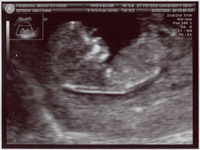

More boy parts (just to be certain) |